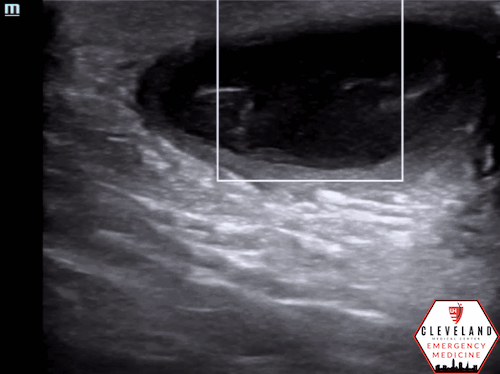

There is a well-circumscribed fluid collection with echogenic debris, consistent with an abscess. Surrounding cobblestoning was also present, supporting concurrent cellulitis in this clinical context. The second lesion demonstrated similar findings of a fluid collection with surrounding cellulitic changes.

Figure 2. Abscess with echogenic debris, swirling with compression.

• Well-circumscribed, anechoic or hypoechoic fluid collection.

• Often contains hyperechoic debris from pus or necrotic material.

• Walls are usually distinct and hyperechoic.

• Probe compression may produce swirling of fluid, known as the “squish sign” (see Figure 2) [8].